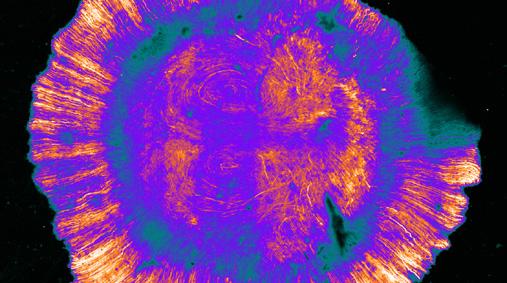

We are moving into a new era in microscopy technology development in which the microscopy technologies, in addition to the imaging function they have always provided, increasingly provide us with additional predictive and prognostic information which would be impossible to derive by any other method.

Oral cancer is one of the fastest developing cancers in the UK, with over 12,000 new cases a year. It is often preceded by oral lesions with approximately 1 in 8 progressing to cancer. In order to optimise therapy, it is crucial to identify those lesions that will progress to cancer. The current best practice is to take tissue biopsies which are then examined by an histopathologist. However, histopathological assessments are labour-intensive, complex, have poor inter-observer reliability, do not completely reflect the risk of long-term malignant transformation and correctly predict cancer progression in only ~40% of cases. Many patients require repeated biopsies which are painful and delay surgery. There is a need to be able to predict with accuracy which patients are going to progress and which are not.

The Liverpool Diagnostic Infrared Wand (LDIR Wand) is based on a patented machine learning algorithm that makes it possible to identify key infrared biomarkers that discriminate between different tissue types (Ingham et al, 2019a). The power of the algorithm was demonstrated by the

early work on oral cancer where it identified two IR biomarkers, 1252 cm-1 and 1285 cm-1, which yielded intensity ratios that discriminated between metastatic oral cancer and lymphoid tissue with sensitivities and specificities of 98.8 ± 0.1% and 99.89 ± 0.01% respectively (Ellis et al, 2021). This research has recently been confirmed by a larger study on 46 tissue cores (Al Jedani et al, 2023) that also provided insight into the chemical composition of this cancer (Al Jedani et al, 2024). When applied to the prognosis of oral cancer lesions, accuracies of ~80% can be achieved – a significant advance on current histopathological techniques (Ellis et al, 2022; Ingham et al, 2022).

In addition to oral cancer, similar problems are present across a range of other cancer types. For example, it is difficult to predict which cases of ductal carcinoma in situ of the breast are going to progress. If these patients can be identified with confidence, treatment can be stratified on the basis of the prediction of progression and many patients could be spared surgery.

Ductal carcinoma-in-situ (DCIS) is the in-situ precursor lesion of invasive breast carcinoma. Preliminary research on a small cohort of specimens supports the hypothesis that the methodology outlined above will identify IR biomarkers which will predict which cases of DCIS will progress or recur. In a study of six DCIS biopsies we have identified eight biomarkers that predict the prognosis with

sensitivities of ~80% and specificities of ~75%, a considerable improvement on current approaches.

A Receiver Operating Characteristic curve (ROC curve) is a graph of the True Positive Rate (Sensitivity) plotted against the False Positive Rate (1 - Specificity) at various decision thresholds. It is one of the most commonly used and accepted methods for assessing the performance of a classification model. In preliminary research on invasive breast

cancer, a study on a cohort of biopsies from 10 patients achieved sensitivities and specificities of 83% and 81% respectively, and an area under the ROC curve of 0.9, in identifying those patients who do not benefit from neoadjuvant therapy. It may also be possible to use this technology to measure the receptor status of breast tumours rapidly.